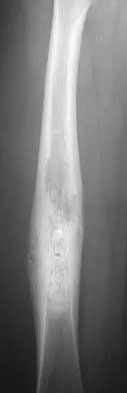

A 10-year-old boy with a history of retinoblastoma now reports right knee pain. AP and lateral radiographs are shown in Figures 3a and 3b. What is the most likely diagnosis?

Explanation

The radiographs show a bone-producing lesion in the femoral diaphysis. The radiographic appearance of small round cell tumors is more permeative with an elevated periosteum and no matrix production. The appearance of this lesion is most consistent with osteosarcoma. Patients who carry the Rb gene are predisposed to osteosarcoma. However, Ewing's sarcoma, primitive neuroectodermal tumor, and osteomyelitis can all occur in this location. Unni KK: Dahlin's Bone Tumors: General Aspects and Data on 11,087 Cases, ed 5. Philadelphia, PA, Lippincott-Raven, 1996, pp 143-160.